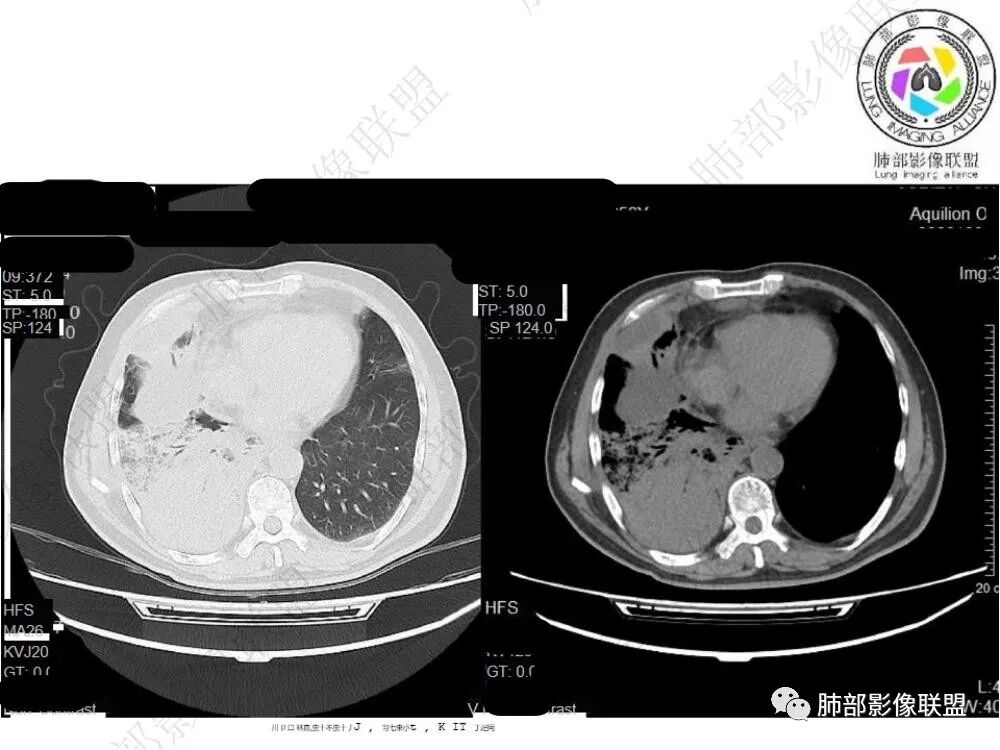

2.影像显示右肺上叶后段及右肺下叶较大范围实性密度为主片状影,边界可分辨,密度较均匀,隐约见小范围低密度(可疑液化区),未见钙化及气囊影。

3.左肺上叶见小片影,边界不清,实性及磨玻璃混合密度。

4.右侧胸腔积液,多包裹局限。

5.纵隔见轻度增大淋巴结。

6.一周后复查变化较为明显。肺部实变影有所吸收,但胸腔积液增加明显,包裹于侧胸壁、纵隔旁及叶间裂。注意右肺下叶因积液推压明显(可惜未能提供薄层图片及矢状位图片)。